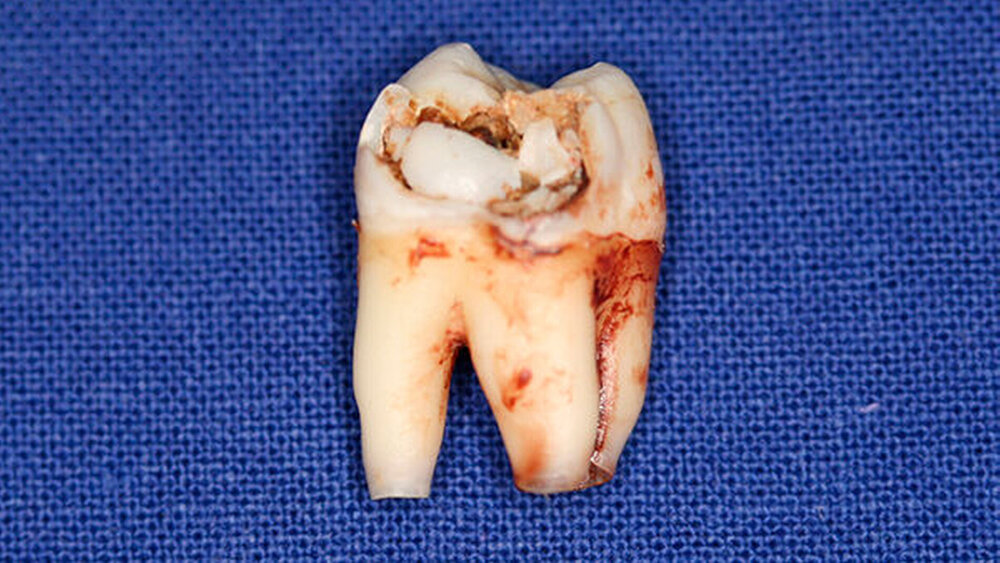

Postoperativ wurden die Zähne in bukko-lingualer Richtung mittels einer diamantbelegten Trennscheibe geteilt. Visuell zeigte sich nun ein großer Hohlraum im koronalen Dentinbereich, sowohl an Zahn 27 als auch an Zahn 47. Die histologische Untersuchung der Zahnfragmente ergab für beide Zähne: Zahnanlagengewebe mit akuter Entzündung (Abbildungen 4 bis 6). Der Patient befindet sich seitdem im regelmäßigen Abstand von sechs Monaten in einem prophylaktischen Recall. Die Abbildung 7 zeigt das postoperative Zahnschema vom 19. August 2015

Der vorliegende Fall zeigt eindrucksvoll verschiedene Stadien der präeruptiven koronalen Resorption (PIR): eine präeruptiv im Röntgenbild sichtbare Transluzenzzone im Dentin des Zahns 47 an der koronalen Schmelz-Dentin Grenze mit intaktem Schmelzmantel und eine große Kavitätenbildung nach Durchbruch des Zahns 27 in die Mundhöhle.

Bei der histologischen Untersuchung der extrahierten Zähne 27 und 47 unseres Patienten wurden Zahnanlagengewebe und Entzündungszellen gefunden. Im Rahmen anderer Untersuchungen konnten resorptive Zellen wie Osteoklasten und Makrophagen an den Rändern der Läsion nachgewiesen werden [Spierer, 2014].